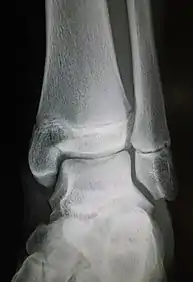

Maisonneuve fracture

The Maisonneuve fracture is a spiral fracture of the proximal third of the fibula associated with a tear of the distal tibiofibular syndesmosis and the interosseous membrane. There is an associated fracture of the medial malleolus or rupture of the deep deltoid ligament of the ankle. This type of injury can be difficult to detect.[1][2]

| Radiograph showing a Maisonneuve fracture of the proximal fibula | |